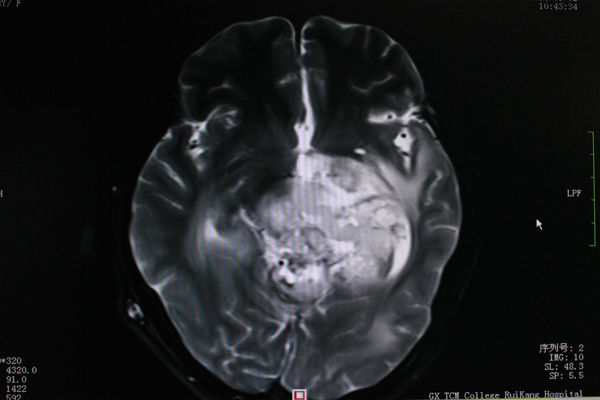

小雨9月MR图像